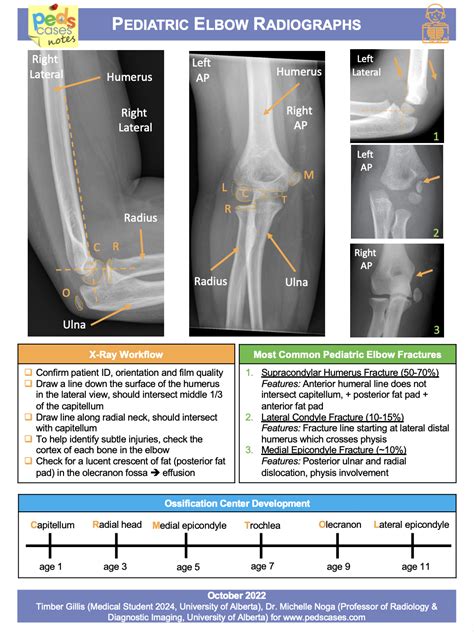

A Bone Age X-ray is a brief, painless imaging procedure that captures a single X-ray image of the left hand and wrist. This specific area is chosen because it contains numerous small bones that develop and change in a predictable sequence throughout childhood and adolescence. As a child grows, the cartilage within these bones gradually hardens, a process known as ossification. Radiologists analyze these changes to estimate the "skeletal age" of the child.

4. Analysis: A pediatric radiologist will review the image, comparing the development of the hand bones to standardized sets of X-rays known as the Greulich and Pyle atlas or the Tanner-Whitehouse method.

When the radiologist analyzes the Bone Age X-ray, they are looking specifically at the epiphyseal plates, often called growth plates. These are the areas of cartilage at the ends of the long bones. As a child approaches the end of their growth spurt, these plates harden and fuse together. Once they are fully fused, bone growth stops. The following table summarizes how skeletal age comparisons are typically interpreted by physicians.